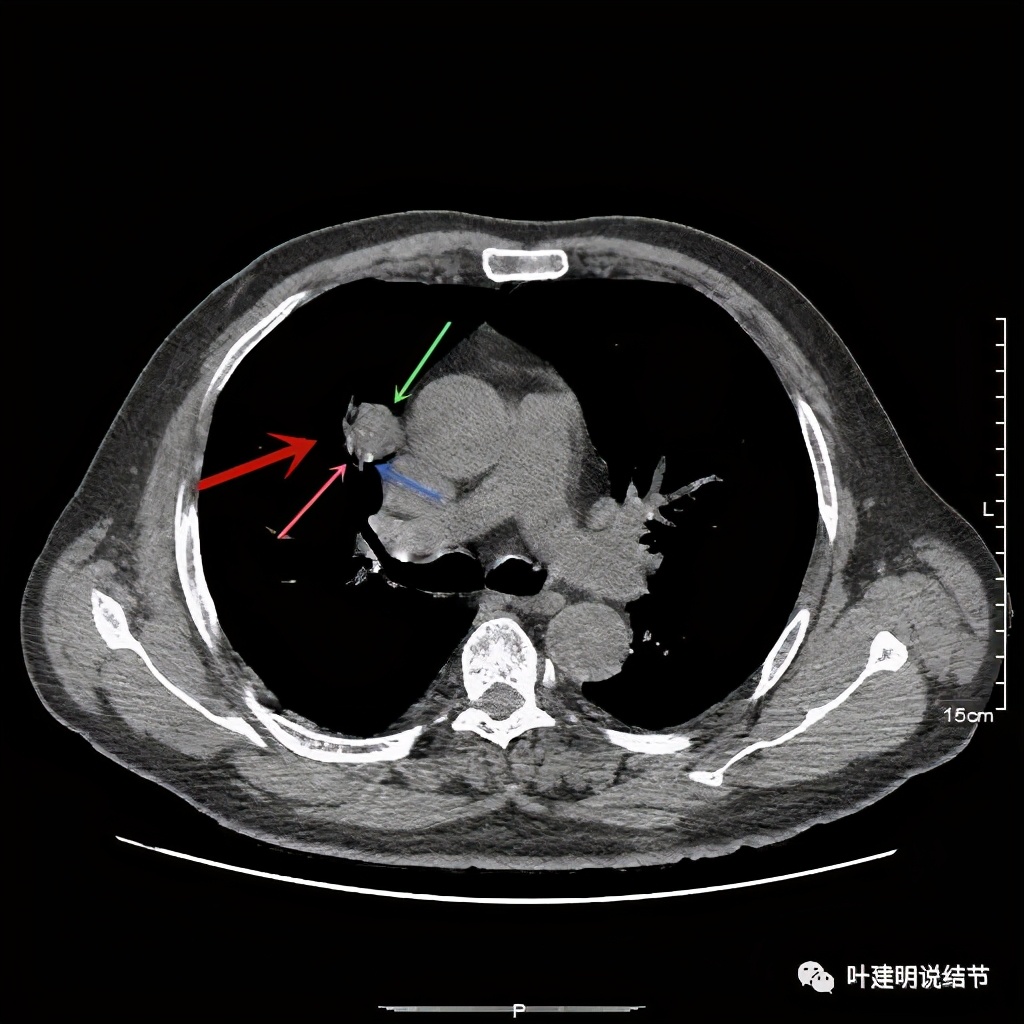

病灶在上图层面似见支气管也是贴壁的。那么增强后又是如何呢?

上图示病灶边缘过于光滑(绿色);局部有点状钙化(蓝色)

上图示病灶边缘过于光滑(绿色);血管贴边(桔色);